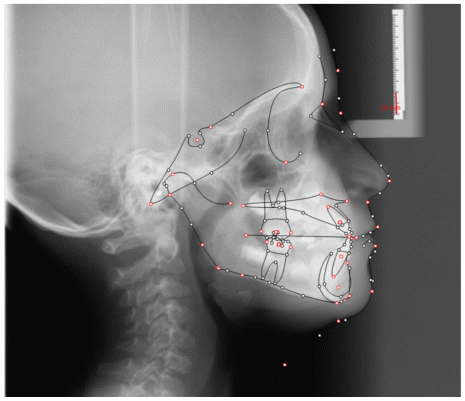

Case 2

The patient was a growing female child who presented during early mixed dentition with an anterior crossbite associated with a deep overbite and a marked sagittal discrepancy (Figures 12–19). The initial clinical examination revealed a negative overjet, complete anterior deep bite, and a functional Class III occlusal pattern. Extraoral assessment showed a flattened facial profile, while cephalometric analysis confirmed a skeletal imbalance characterized by increased SNA and SNB values, an ANB of 0°, negative Withs appraisal, and significant dentoalveolar compensations, including proclination of both upper and lower incisors (Table 3). The vertical pattern was predominantly hypodivergent, suggesting a high risk of unfavorable mandibular growth progression if left untreated. Given the patient’s young age and growth potential, an early interceptive treatment was planned to use the AMCOP® TC appliance, with the aim of correcting the anterior crossbite, improving neuromuscular balance, and guiding sagittal and vertical development during growth. The appliance was worn nightly and for additional daytime hours, according to patient compliance.

After 18 months of treatment, a clear clinical improvement was observed. Intraoral examination demonstrated complete correction of the anterior crossbite, with establishment of a positive overjet and normalization of the anterior occlusal relationship. The deep bite was reduced, allowing more functional anterior guidance. Occlusal relationships improved toward a stable dental Class I, and the need for excessive dentoalveolar compensation was reduced. Cephalometric reassessment showed an overall improvement in sagittal relationships and incisor inclinations, with a trend toward normalization of the previously altered parameters. These findings indicate that early functional therapy with the AMCOP® TC appliance was effective in intercepting the developing Class III malocclusion, improving occlusal function, and potentially reducing the severity of future skeletal discrepancies (Table 4).

This case highlights the importance of early diagnosis and timely functional intervention in growing patients, demonstrating how interceptive treatment can favorably influence occlusal development and facial balance during critical growth phases.